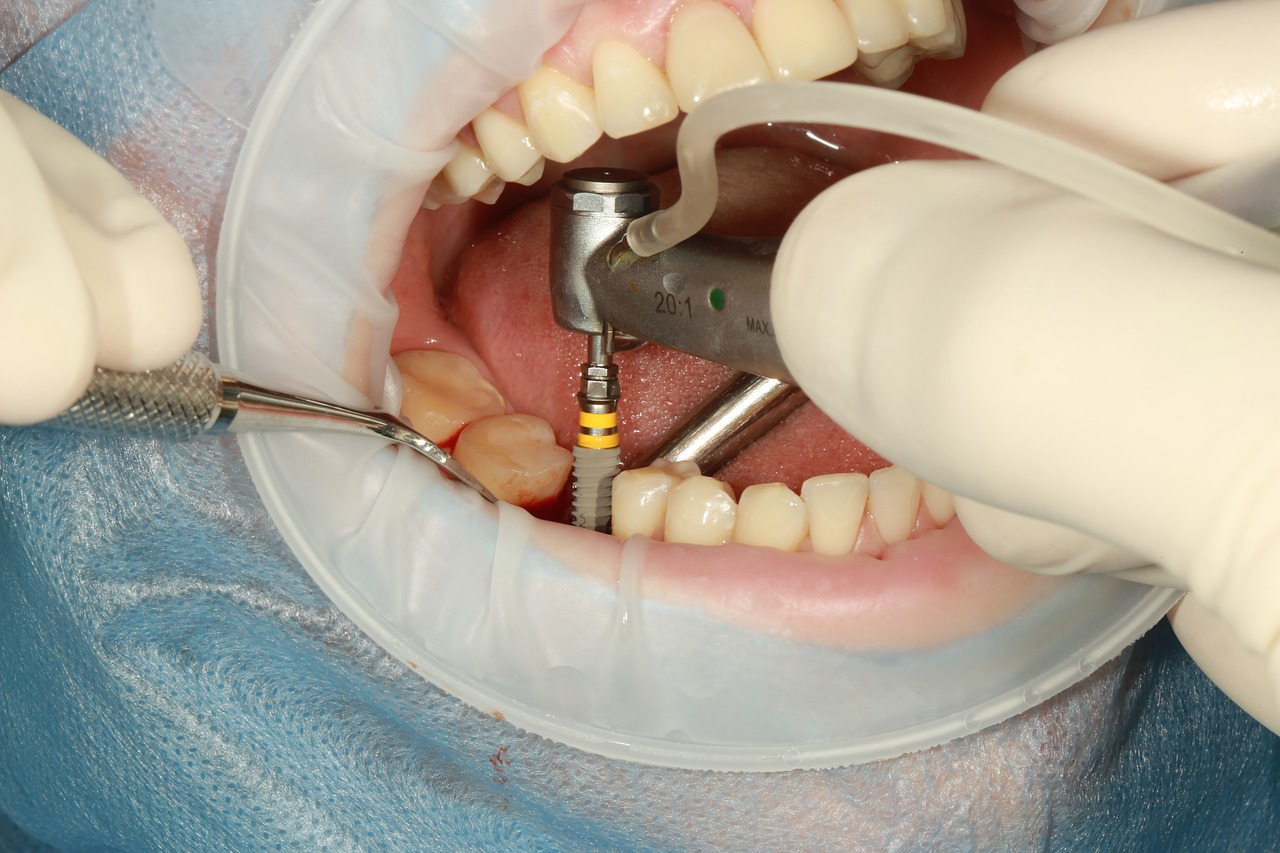

…ma soprattutto, non dimenticare di fareuna visita periodica di controllo al Centro Odontoiatrico Idea!